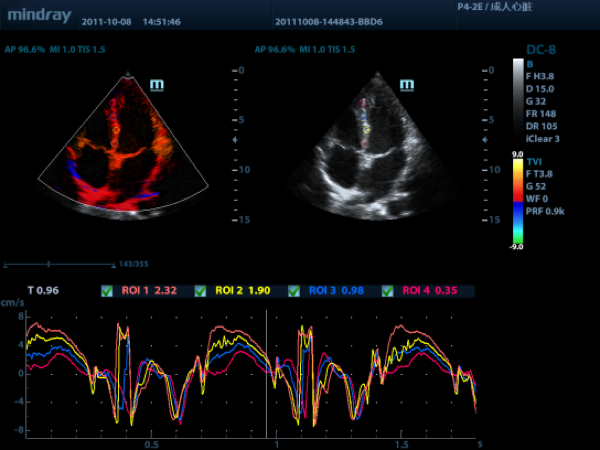

Режим тканевого допплера поставляется под разными наименованиями в зависимости от производителя ультразвукового прибора (TDI, DTI, TSI и пр.). Режим представляет собой допплеровскую визуализацию движения тканей: на двумерной картине B-режима с помощью цветового картирования отображается пространственное распределения скоростей движения тканей в исследуемой области. Основное применение данного режима – исследования на сердце и регистрация сократительной функции миокарда.

Дополнительно, режим тканевого допплера может быть укомплектован функцией количественного анализа сократимости, что значительно облегчает работу диагноста при подобных исследованиях.

Рассмотрим режим тканевого допплера на изображениях, полученных на приборе Mindray DC-8 с активированными опциями TDI (режим тканевого допплера) и TDI QA (количественный анализ в режиме тканевого допплера).